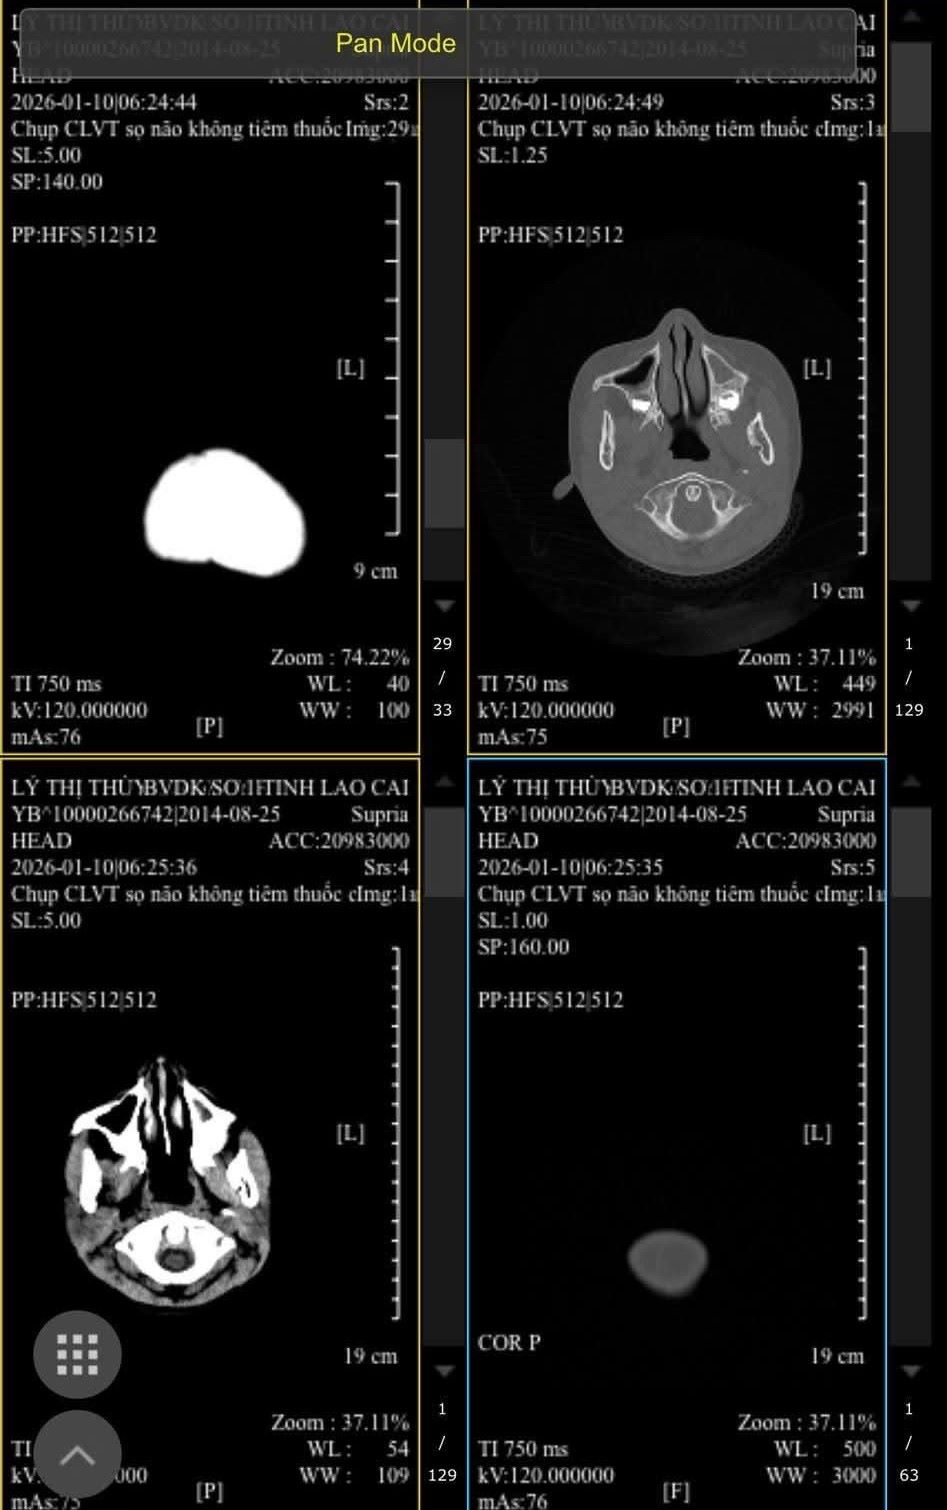

Sáng 12.1, trao đổi với phóng viên, anh Lý Kim Lâm (bố cháu C) cho biết: Từ hôm bị bạn đánh đến giờ cháu vẫn đau đầu, chóng mặt. Trên người vẫn còn nhiều vết bầm tím, hiện điều trị tại Bệnh viện Đa khoa số 1 Lào Cai. Các bác sĩ chẩn đoán cháu bị chấn thương ngoài da và chuẩn bị được xuất viện.

"Gia đình sẽ đưa cho cháu lên bệnh viện tuyến trung ương kiểm tra, điều trị do lo ngại ảnh hưởng đến phần đầu khi liên tiếp bị bạn đấm, đá nhiều lần vào vị trí nguy hiểm", anh Lâm nói.